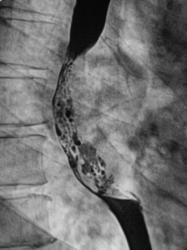

Рентгенограммы и их фрагменты.

Ниже представлены прицельные рентгенограммы пищевода, произведенные в процессе исследования данного пациента, в ортоположении водной взвесью сернокислого бария обычной консистенции.

Ниже рентгенограммы, произведенные на трохоскопе с применением сметанообразной и пастообразной контрастной взвеси.